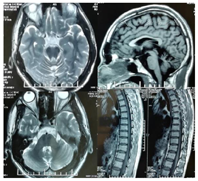

入院后进行了如下检查:眼底照相、影像学检查(头和颈椎MRI、周围神经超声)、神经电生理检查(周围神经传导速度、体感诱发电位、视觉和脑干听觉诱发电位、眼震电图检查)。取患者外周血提取DNA进行二代测序(测序机构:北京迈基诺医学检验所),捕获芯片覆盖Friedreich共济失调及遗传性痉挛性截瘫等致病基因,并取患者父母外周血提取DNA并对SACS突变基因进行家系验证。眼底检查提示双侧静脉阻塞,有髓神经纤维增生,视盘发育异常(图2)。头颅+脊髓磁共振T2WI和T2 FLAIR示小脑萎缩,蚓部及旁蚓部明显,小脑中脚可见对称长T2信号影,脑桥相对饱满,小脑明显萎缩,上胸髓萎缩变细(图3)。周围神经超声:双侧臂丛神经、坐骨神经及右侧腓总神经内径普遍增粗,疑有慢性损伤后修复(图4)。神经电生理检查:主要表现为四肢运动感觉神经损伤,感觉受损为著,右正中神经F波潜伏期稍延长、出现率降低、波幅降低,双胫神经H反射未测出;右手第一骨间肌、左胫前肌神经源性损害,左股内侧肌MUP个别波幅高。眼震电图检查提示视跟踪试验Ⅲ型;凝视试验:暗环境向左凝视可见2度左向眼震;变位试验:DH左20度下跳眼震6 s,后出现4度上跳眼震20 s,回原位未见眼震,深悬头位有5度上跳眼震7 s。基因检查:二代测序检测基因目标区覆盖度99.7%,目标区平均深度为149.94,目标区平均深度>20×、比例为99.2%。测序发现该患者SACS基因存在c.7656T>G(p.N2552K)和c.2387T>A(p.L796X)两个突变,根据ACMG指南,c.7656T>G(p.N2552K)突变判定为临床意义未明;c.2387T>A(p.L796X)判定为无义突变,对蛋白功能影响可能较大,为疑似致病性突变。Sanger测序结果显示母亲携带SACS基因c.7656T>G(p.N2552K)杂合突变,父亲携带c.2387T>A(p.L796X)杂合突变(图5)。

神经电生理检查提示患者有多发感觉、运动以及自主神经受累症状,这与之前已发表病例类似。当周围神经损伤严重锥体束损害症状常常被掩盖,下肢痉挛并不明显,出现下肢肌张力及腱反射均降低,甚至可出现尿急、尿失禁、勃起功能障碍,患者还可以伴随癫痫、智力和听力受损、精神异常,而该患者均无相似症状,提示该患者仍处在病情较轻的阶段。许多患者眼底检查可见视盘边缘发出黄色条带状高髓鞘纤维,此表现也见于该患者。该患者可见双侧静脉受阻,可能与增厚的神经纤维压迫有关。此外,光学相干成像还可见视网膜纤维增厚,这些可能是ARSACS特征性表现,该患者无此表现。混合型视网膜异常对ARSACS是高度特异性的,视网膜的增生是由于异常视网膜髓鞘发育所致。未来OCT可能为ARSACS的临床诊断提供潜在的生物标志物。小脑半球及上蚓部萎缩,脑桥旁正中线性低信号条带,小脑中脚增厚、丘脑周围高信号环被认为是ARSACS特征性的影像学表现,该患者也具备部分特点。值得注意的是,影像学上,该患者小脑萎缩累及前庭小脑及绒球小结叶,这在以往报道中并未出现。此例病例发现脊髓萎缩波及上胸髓,但文献报道脊髓萎缩常见多累及颈髓,少有胸髓萎缩。此外部分文献发现还可出现胼胝体、脑干以及大脑皮质的萎缩,但该患者未出现上述表现。